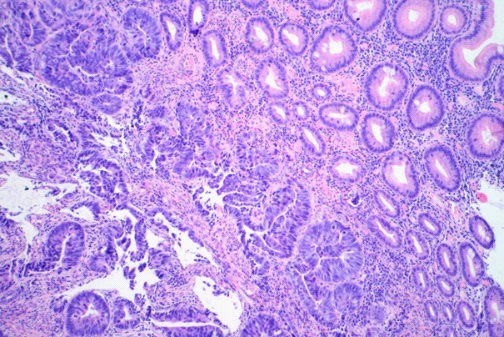

A 73 years old male patient was admitted to our thoracic department with the solitary pulmonary nodule in the lower right lobe (Figure 1).

The nodule was revealed by the X-Ray examination because of the continuous cough and left chest pain. There were no dysphagia and any clinically significant laboratory changes. In anamnesis the oesophagocoloplasty for squamous cell carcinoma (SCC) of the oesophagus (pT2N1Mo) with adjuvant radio-chemotherapy was performed 10 years before. We performed videoassisted (VATS) wedge resection of the right lower lobe with the lesion. The pathology finding was colon type adenocarcinoma (Figure 2).

Figure 1: Computer tomography with a solitary pulmonary node in lower lobe right (arrow).